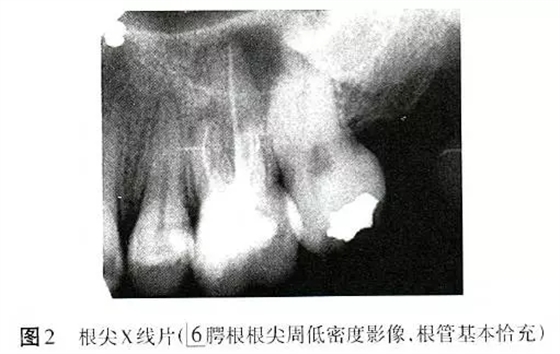

X線片顯示6根管恰充,腭根根尖周低密度影像,直徑6mm×6mm(圖2)。為排除根折,拍攝錐形束CT(CBCT),除發(fā)現(xiàn)MB2遺漏且未見(jiàn)明顯根折以外,意外發(fā)現(xiàn)6根尖周骨病損范圍遠(yuǎn)較X線片所顯示的更廣,累及全部牙根,且患牙頰側(cè)硬骨板缺損(圖3)。診斷:6根管治療后疾病(post-treatmentendodonticdisease,PTED)。